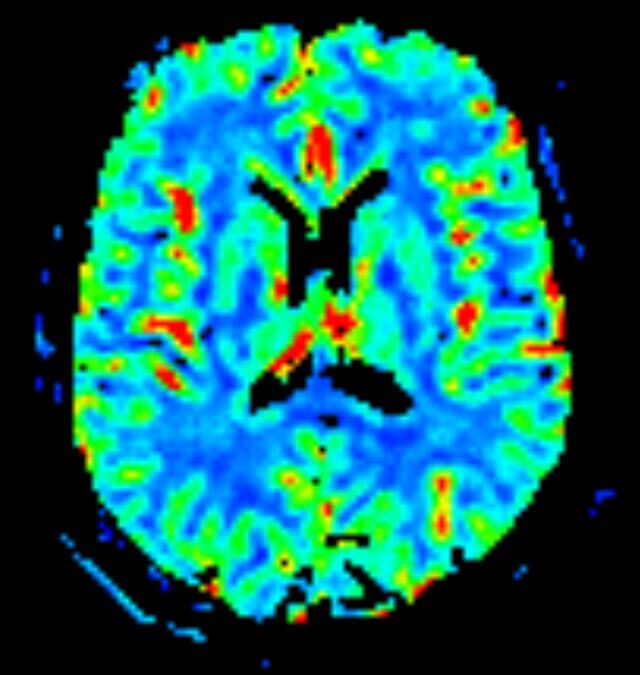

Abdomen/Becken

• Darm

• Darstellung bzw. Kontrolle im Verlauf bei perianalen Fisteln und Abszessen

• Verlaufskontrolle des Lokalbefundes nach Rektumentfernung bei Karzinom